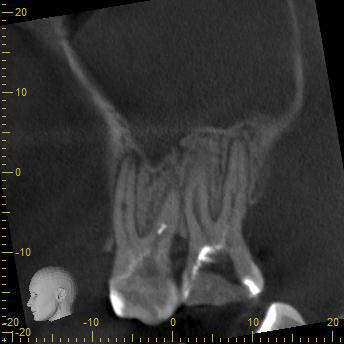

BN2627_DVT (11 von 17) Veröffentlicht 1. Dezember 2014 am 344 × 344 in Unerwartete Anatomie Zahn 26, 27- die WF